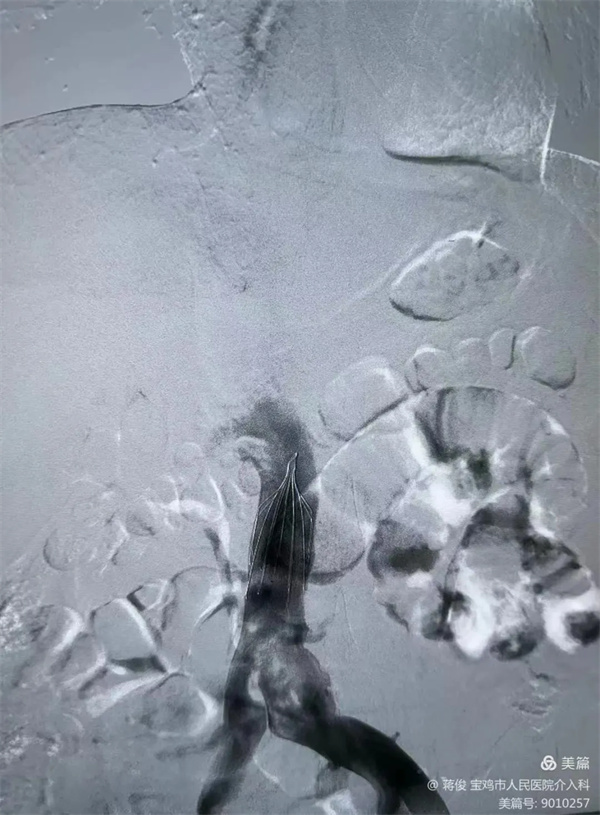

肺動脈DSA造影提示肺動脈主干及分支大量血栓,予以肺動脈造影、血栓溶解、肺動脈碎栓

置入下腔靜脈濾網,預防下肢靜脈血栓再次脫落